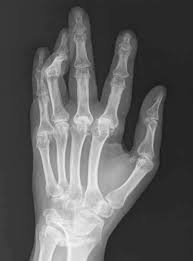

적절한 시기에 치료를 받지 못하면 관절이 변형되고, 변형된 관절은 회복이 불가능하기 때문에 조기 진단과 치료가 매우 중요하다고 한다.

류마티스관절염은 병이 진행될수록 관절과 관절 주위조직의 손상을 유발하고, 결국에는 관절의 변형과 운동장애를 초래한다고 한다.

이미 손상된 관절은 이전 상태로 되돌리기 힘들고 손가락 관절에 장애가 생기면 일상생활을 하는데 지장이 커서 초기에 발견해 치료를 하는 것이 매우 중요하다고 한다.